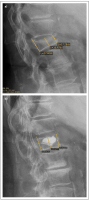

Möglichkeiten der direkten Zementinjektionstechnik bei Wirbelkörperfrakturen - Drei Fallbeschreibungen der Radiofrequenz-Kyphoplastie (RFK) mit ultrahochvikösem Knochenzement

Journal für Mineralstoffwechsel & Muskuloskelettale Erkrankungen 2012; 19 (3): 124-130 Volltext (PDF) Summary Praxisrelevanz Abbildungen